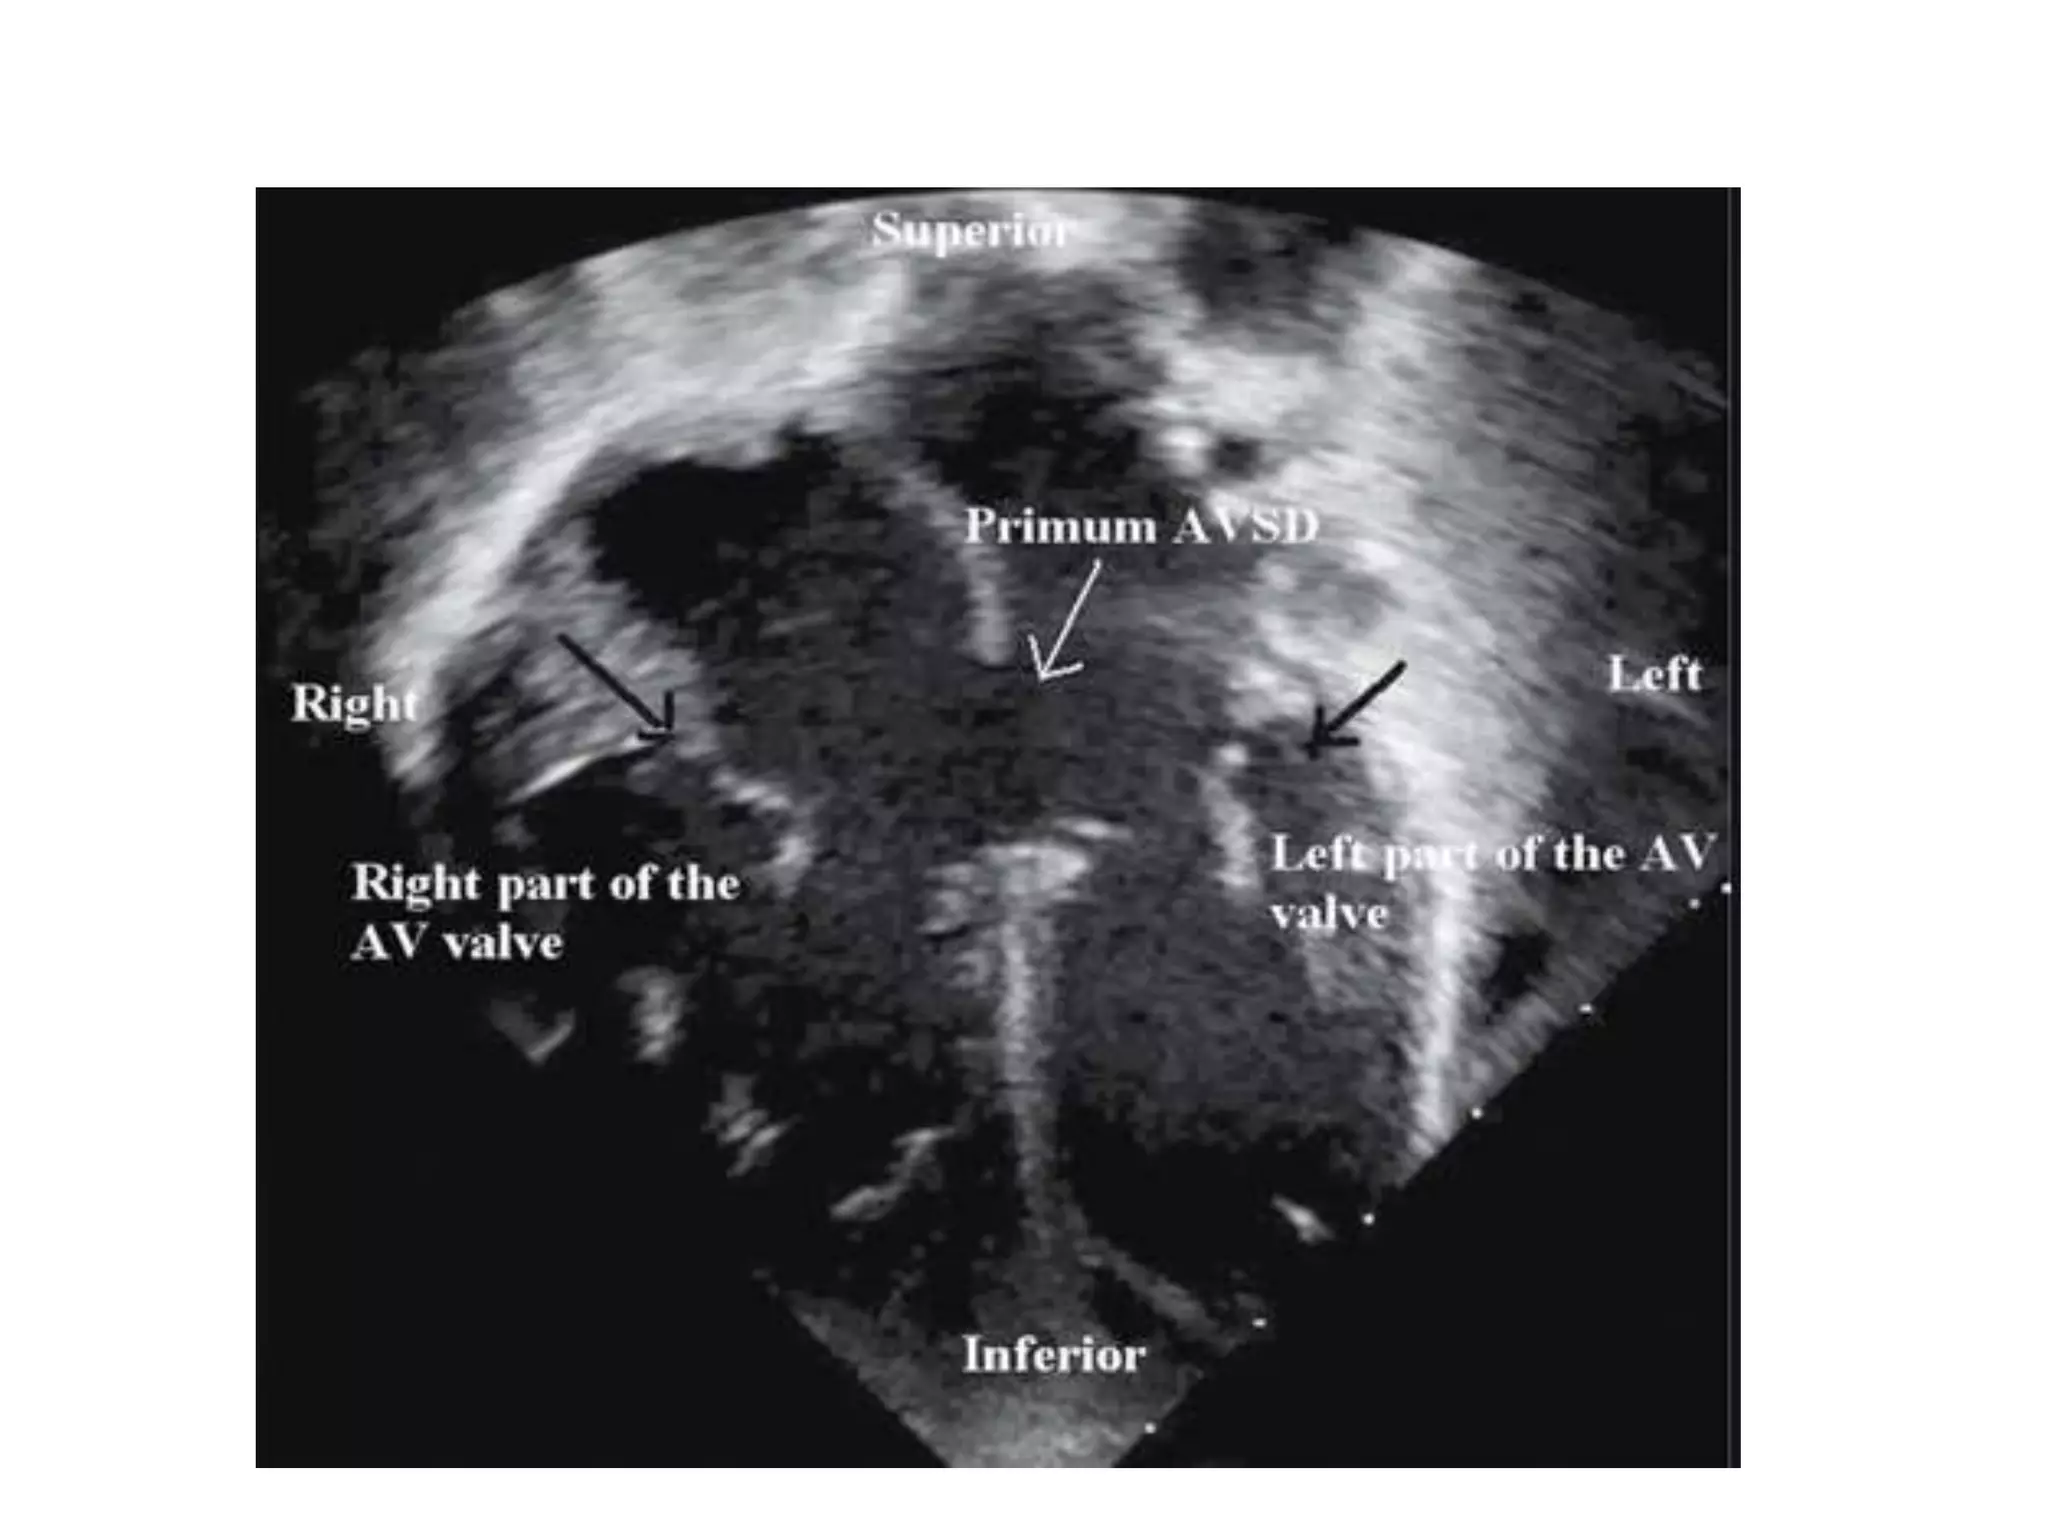

Echocardiography

• The internal cardiac crux is the most consistent imaging landmark

• Apical four-chamber imaging plane clearly visualizes the internal crux

• The primum ASD is seen as an absence of the lower IAS

Echocardiography • Primary imagingtechnique for diagnosing AVSD • The internal cardiac crux is the most consistent imaging landmark • Apical four-chamber imaging plane clearly visualizes the internal crux • The primum ASD is seen as an absence of the lower IAS